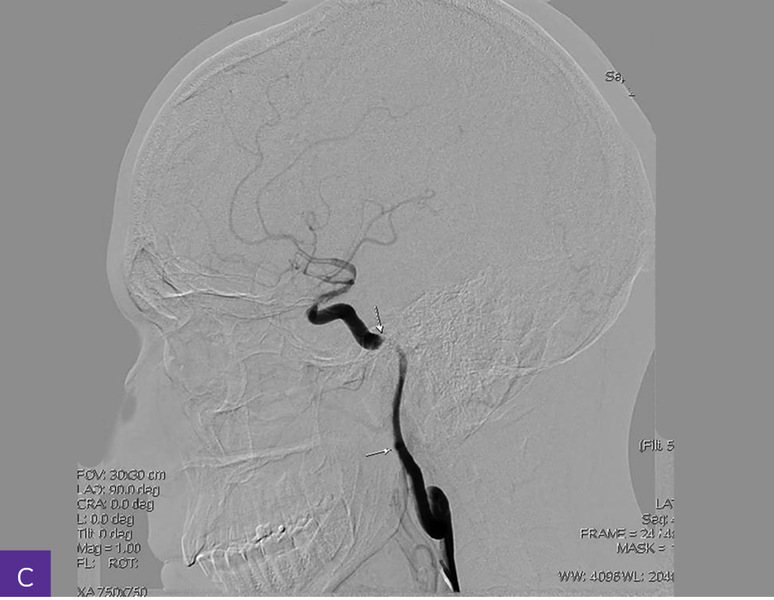

Rycina 4A-C. Cyfrowa angiografia subtrakcyjna (DSA). Widoczna przewlekła niedrożność nadklinowych odcinków obu tętnic szyjnych wewnętrznych, z wzorcem unaczynienia końcowego typu moyamoya, niedrożnością odcinków M1 obu tętnic środkowych mózgu, hipoplazją odcinków A1 obu tętnic przednich mózgu i krążeniem obocznym

Diagnostykę poszerzono o badanie cyfrowej angiografii subtrakcyjnej (DSA – digital subtraction angiography), która uwidoczniła przewlekłą niedrożność nadklinowych odcinków obu tętnic szyjnych wewnętrznych o nieznanej etiologii, z wzorcem unaczynienia końcowego typu moyamoya, niedrożnością odcinków M1 obu tętnic środkowych mózgu, hipoplazją (i/lub zastępczą neoangiogenezą) odcinków A1 obu tętnic przednich mózgu i krążeniem obocznym – głównie przez kolaterale obwodowe obu tętnic tylnych mózgu, po stronie prawej wspomaganym przez napływ z tętnicy oponowej środkowej i ocznej (ryc. 4).